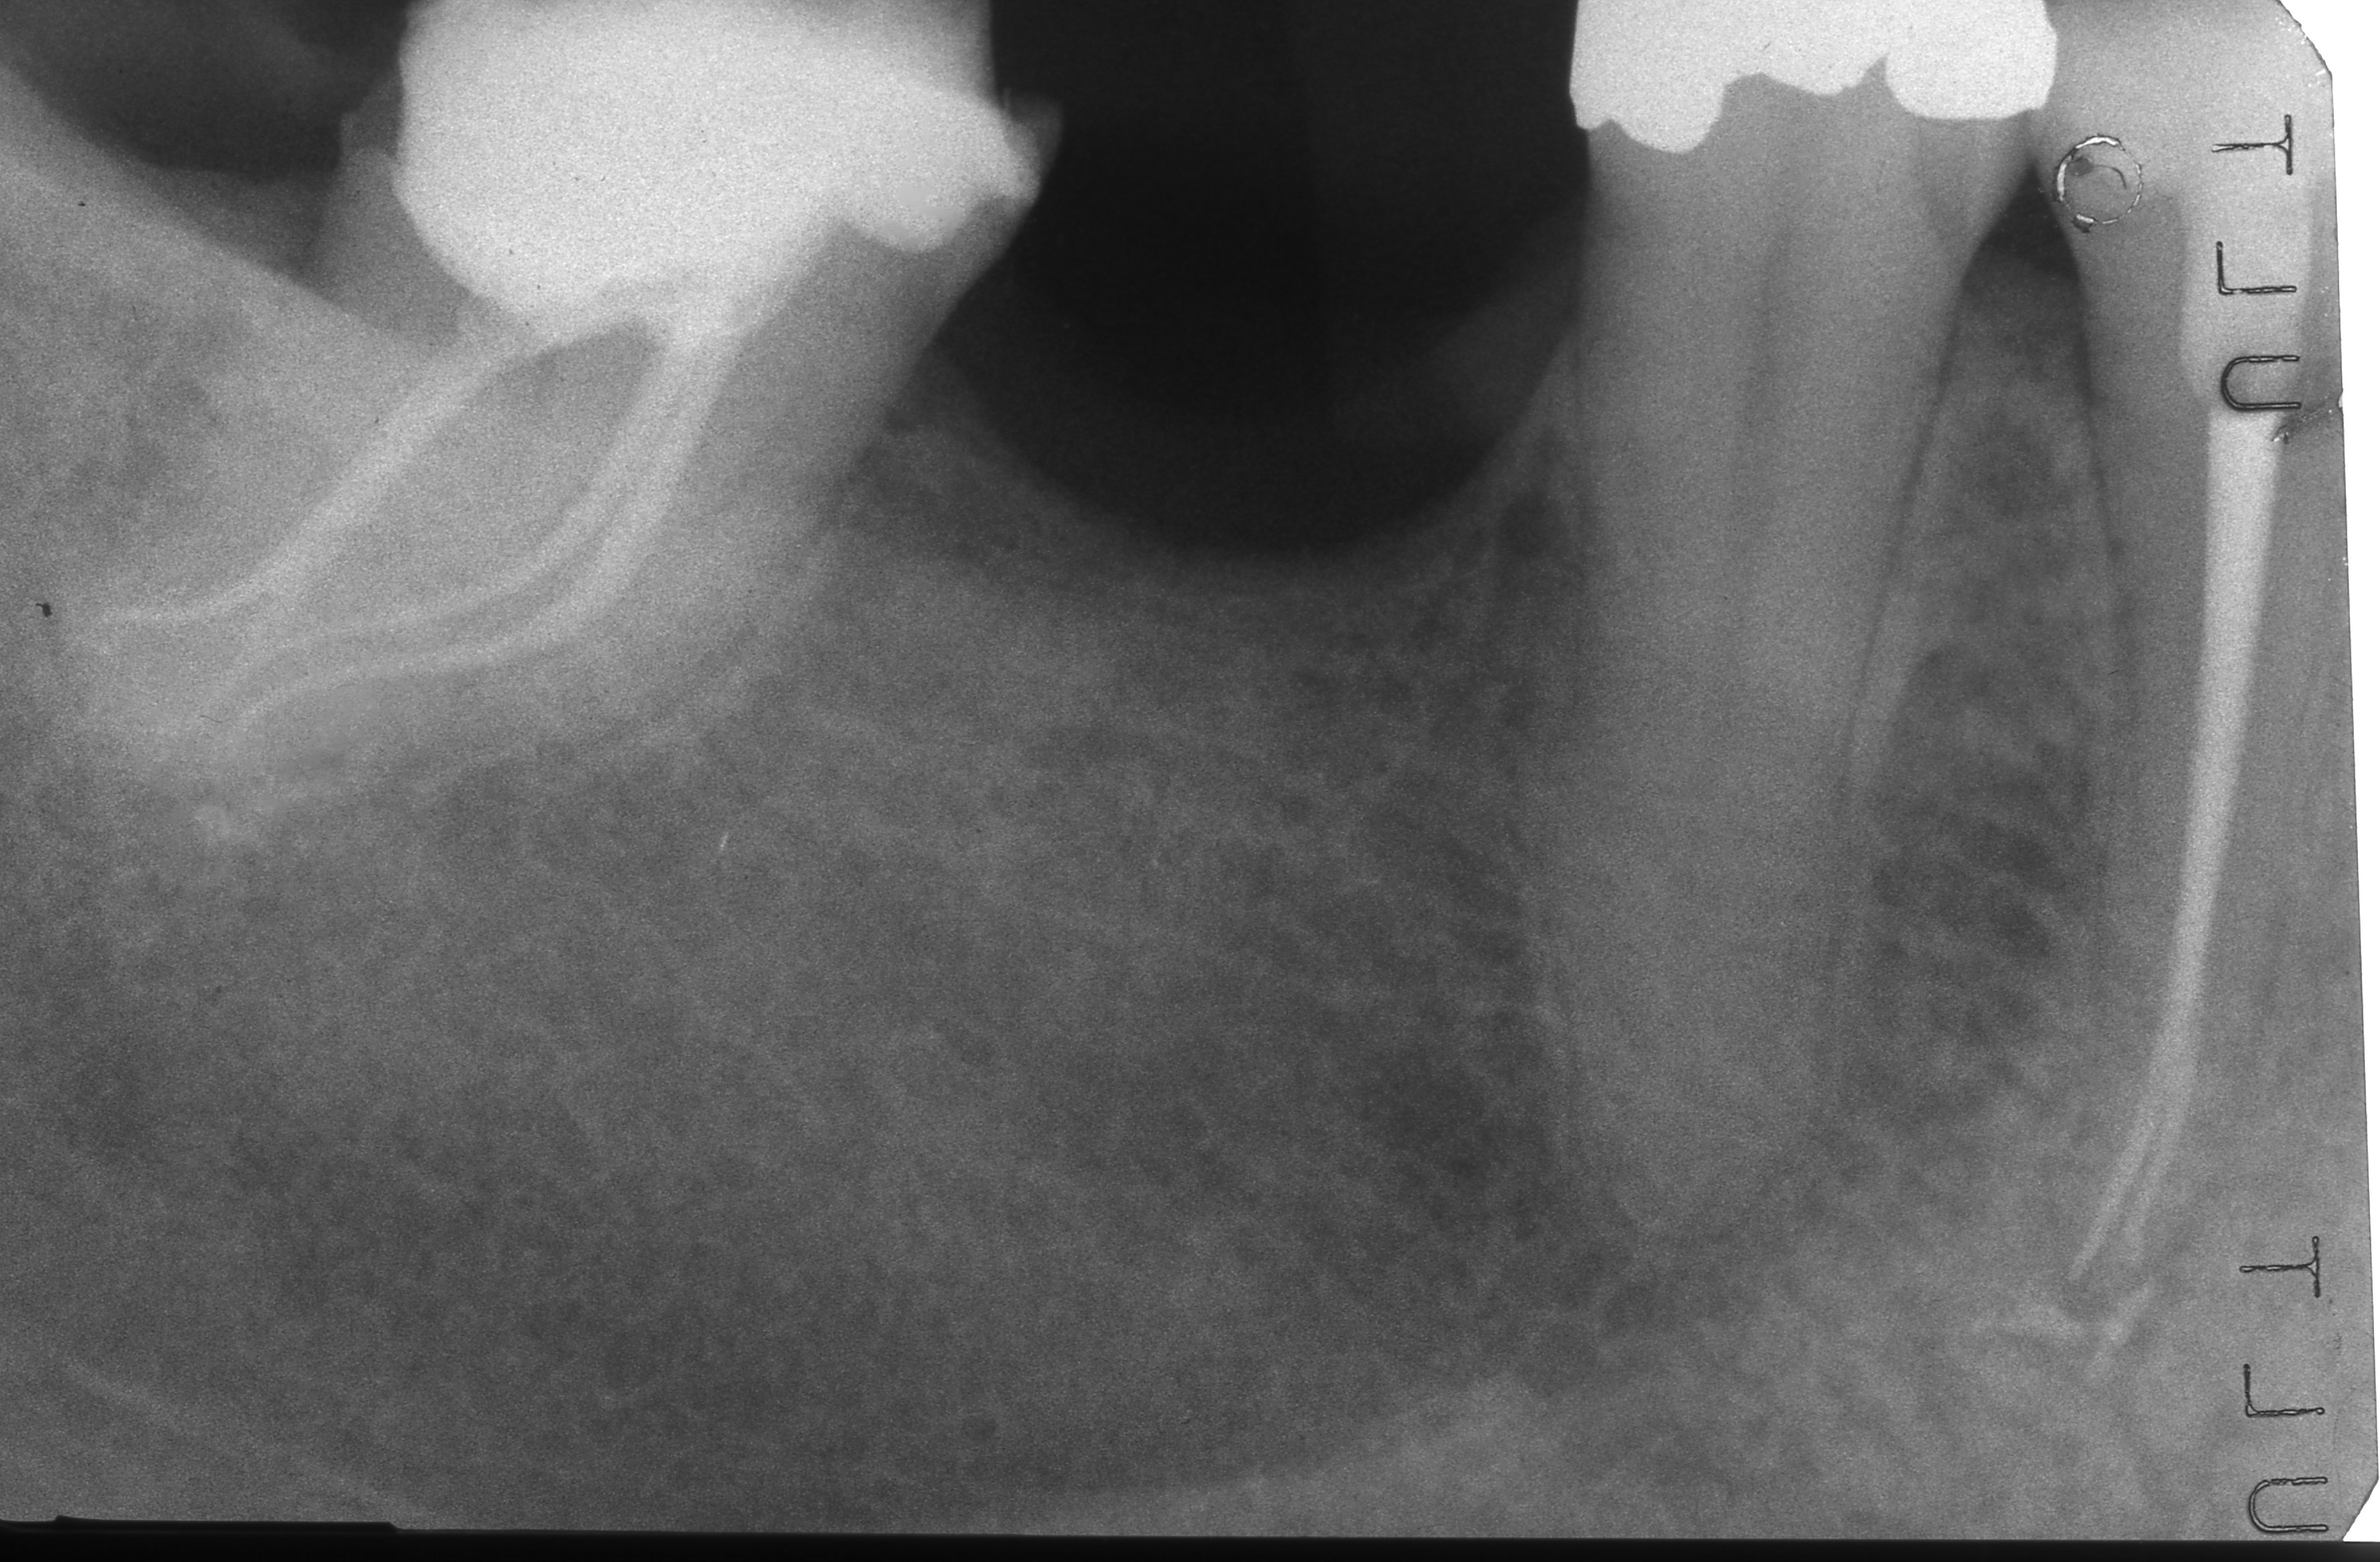

Apertura della corona fino ad arrivare alla camera pulpare (tale trattamento viene eseguito tramite anestesia locale). Si rimuove la polpa e si cercano i canali radicolari del dente, una volta trovati si estirpano i nervi. Si allargano e si puliscono i canali del dente, (tramite strumenti al Nichel titanio o strumenti manuali) prendendo anticipatamente le misure dei canali (per non uscire oltre apice). Si disinfettano i canali e si eseguono vari lavaggi tra un passaggio e un altro per elimininare il fango dentinale. Il medico a questo punto verifica la possibilità di chiudere definivamente i canali o lasciare il dente in prova, inserirendo nei canali un disinfettante e eseguendo una chiusura provvisoria. Al momento di chiudere il dente definivamente, questo viene preparato rieseguendo le misure dei canali da chiudere ed usando per la stessa lunghezza del canale, un cono di guttaperga del diametro necessario. Si scalda il cono in guttaperga e si inserisce nel canale. Durante il trattamento endodondico vengono effettuati una serie di esami radiografici per verificare i risultati, le lunghezze, la forma dei canali.

L'esame radiografico, fondamentale per porre diagnosi in odontoiatria, in endodonzia è irrinunciabile perché è l'unico strumento che ci permette di "vedere" all'interno della radice del dente, è quindi molto importante la possibilità di effettuare lastre con apparecchiature digitali che emettono un quarto della dose di raggi emessa da un radiografico tradizionale e che permettono di conservare la radiografia endorale in una cartella informatica del paziente senza possibili alterazioni nel tempo.